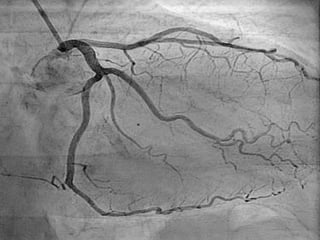

 Coronary Angiography

 History collection Physical Exam and  ECG (Electrocardiogram)  MRI  Echocardiography  Coronary Angiography